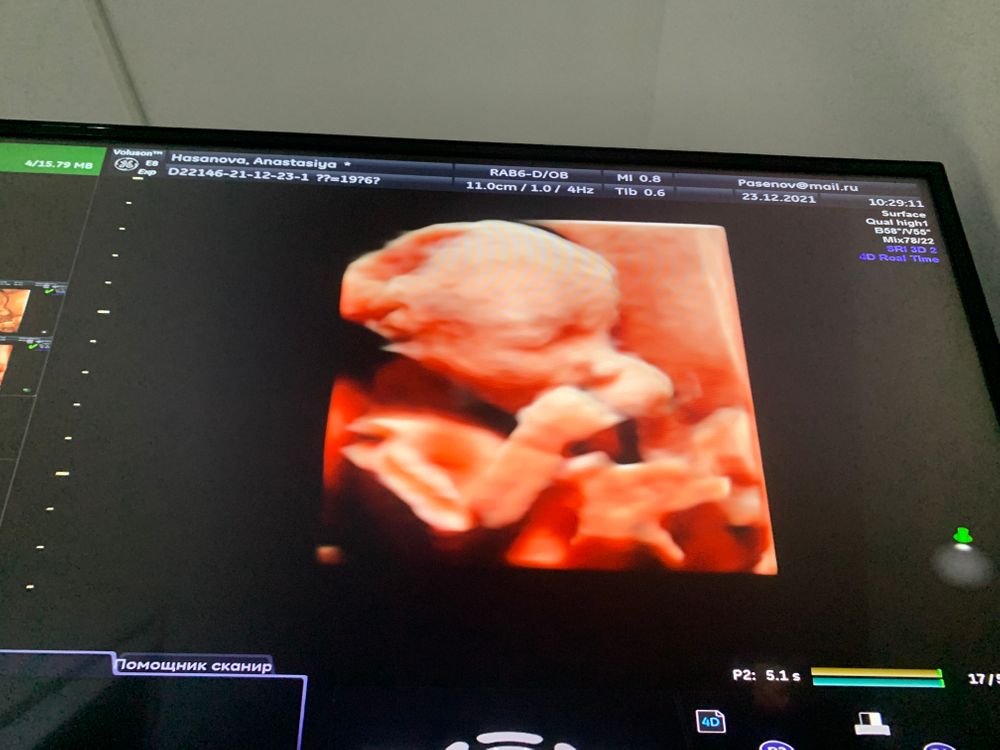

На каком сроке лучше делать 4D узи?

УЗИ, КТГ, доплерДевочки, на каком сроке лучше всего потратиться на 4d узи?)) в какое время малыши уже прям человеки?)) у меня сейчас 20 недель, хочу сходить, но начиталась отзывов, что на этом сроке детки ещё «страшненькие»😃🙈 если кто то делал примерно на моем сроке, поделитесь фоточками пожалуйста🥰 если хотите можно в личку)

На втором скрининге в 19+1 врач включила 4D, хороший человечек уже. Фото в дневнике у меня есть

Я ведусь платно, поэтому каждое узи есть вид в 4д. С 20 недели очень милые фотки) Но если вам отдельно придётся за это доплачивать, то лучше после 22-24.

26-28 недель самое хорошее время, как говорят сами узисты. Нам узист при каждом визите делала, конечно, самые большие щёчки в 32 недели)

Все скрининги и УЗИ проходила в самарской школе ультразвука. На каждом обследовании делали 4D. В 26-28 нед самые лучшие фотки, у малыша уже щечки пухленькие. На более позднем сроке малыш с трудом помещается в экран. В 20 нед еще похож на инопланетянина))))

В 20.0 ровно по мес (20.2 по узи) включали на скрининге 3-4д режим, был такой)